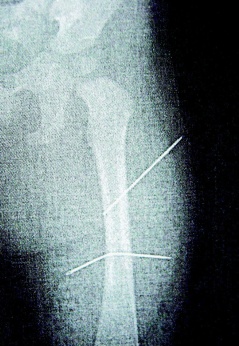

隔月27日,該女子又見外甥女哭鬧不停,拿蒼蠅拍朝著外甥女背部連打數十下,造成女娃背部瘀傷。經女娃母親發現后送醫救護,院方為女童進行X光片照射后,才發現女娃左大腿里竟有兩根縫衣針。